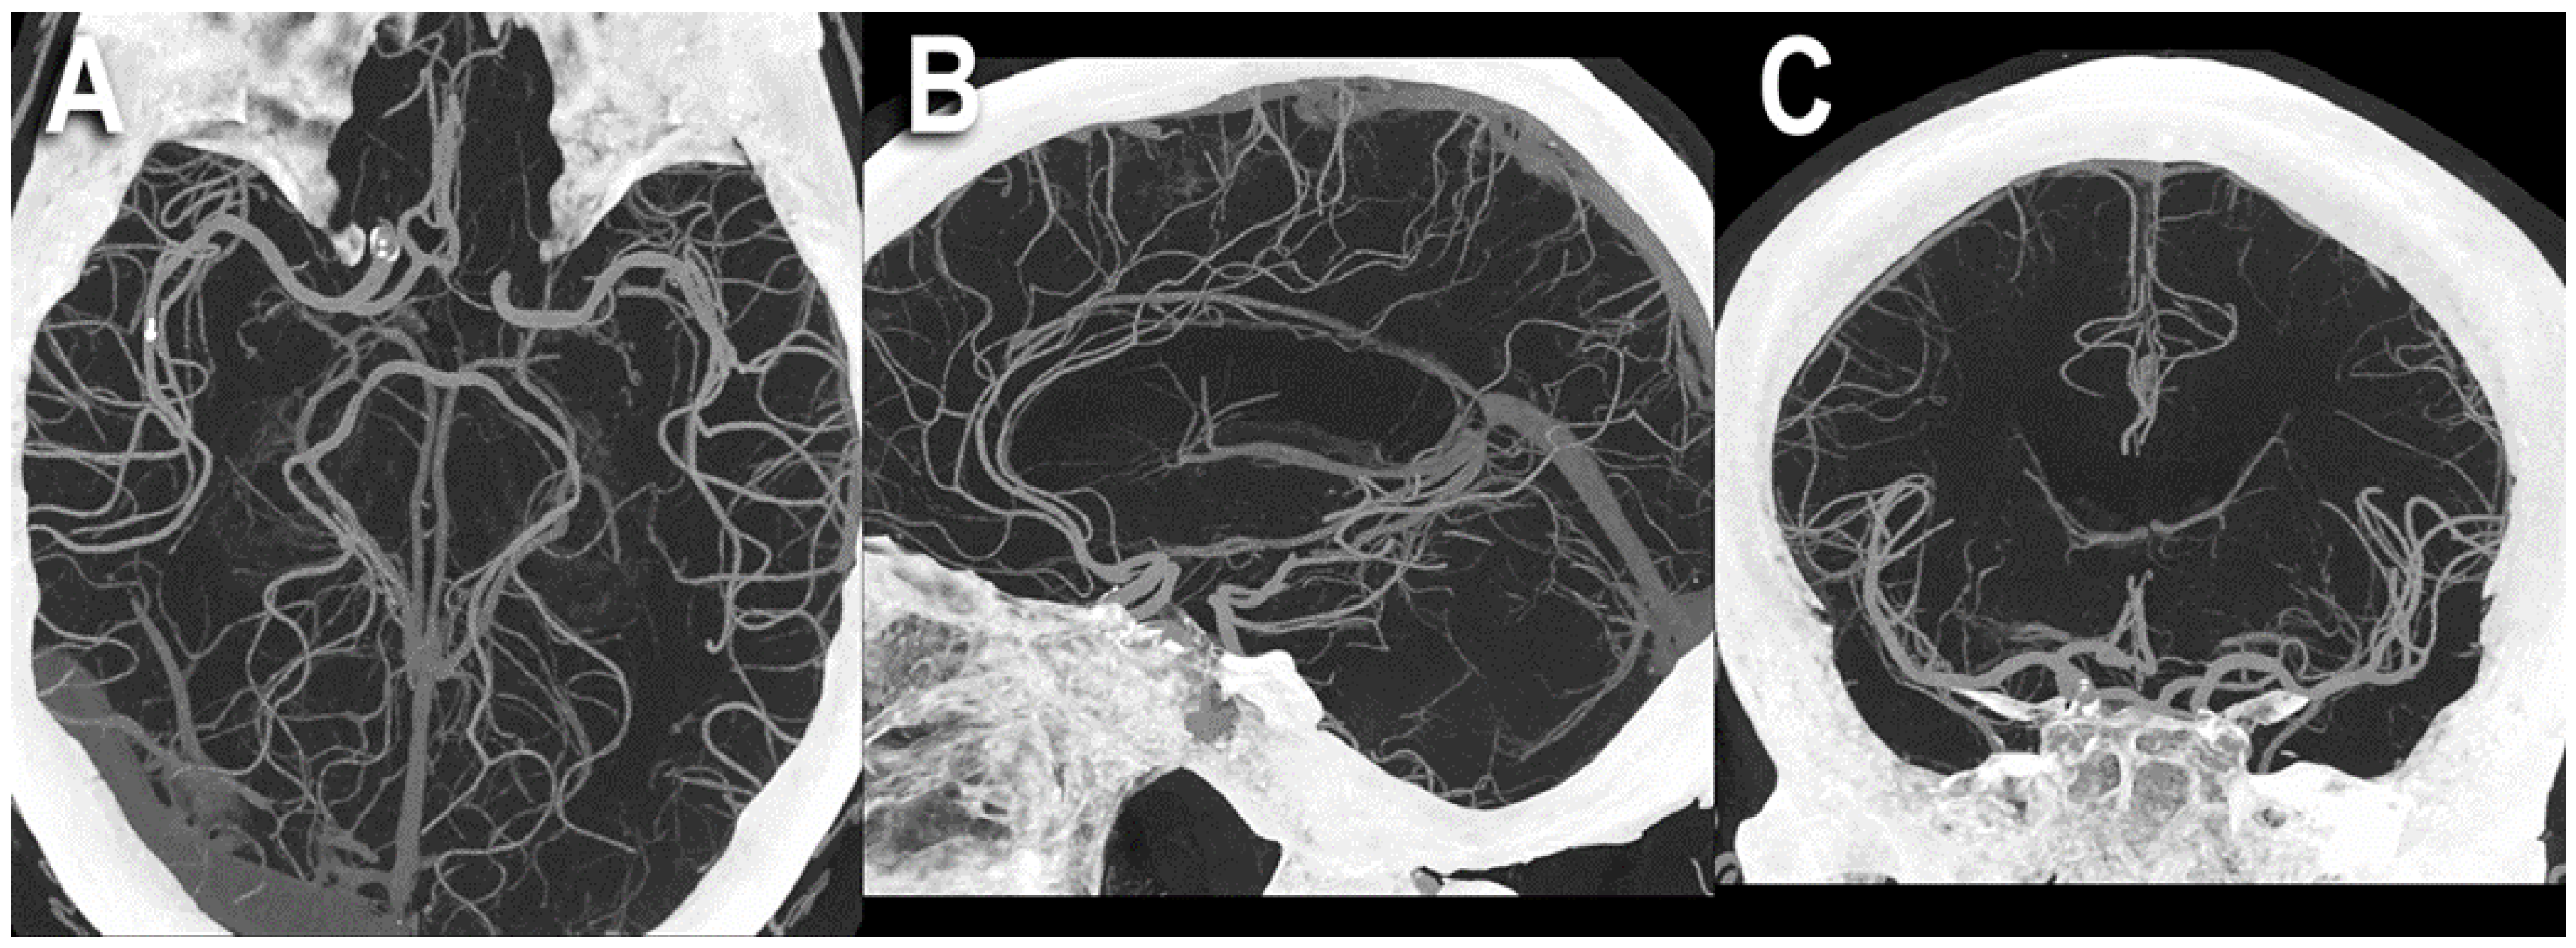

6.3. Increased Resolution

- Michael, A.E.; Boriesosdick, J.; Schoenbeck, D.; Lopez-Schmidt, I.; Kroeger, J.R.; Moenninghoff, C.; Horstmeier, S.; Pennig, L.; Borggrefe, J.; Niehoff, J.H. Photon Counting CT Angiography of the Head and Neck: Image Quality Assessment of Polyenergetic and Virtual Monoenergetic Reconstructions. Diagnostics 2022, 12, 1306. [Google Scholar] [CrossRef]

| Michael et al. [28] | 2022 | In vivo (human) | 37 | Iodine-only images | The most favorable contrast-to-noise-ratio and signal-to-noise-ratio were detected in the PER and low keV MER. In the qualitative image analysis, the PER was superior to the MER in all rated criteria. For MER, 60–65 keV was rated as best image quality. |